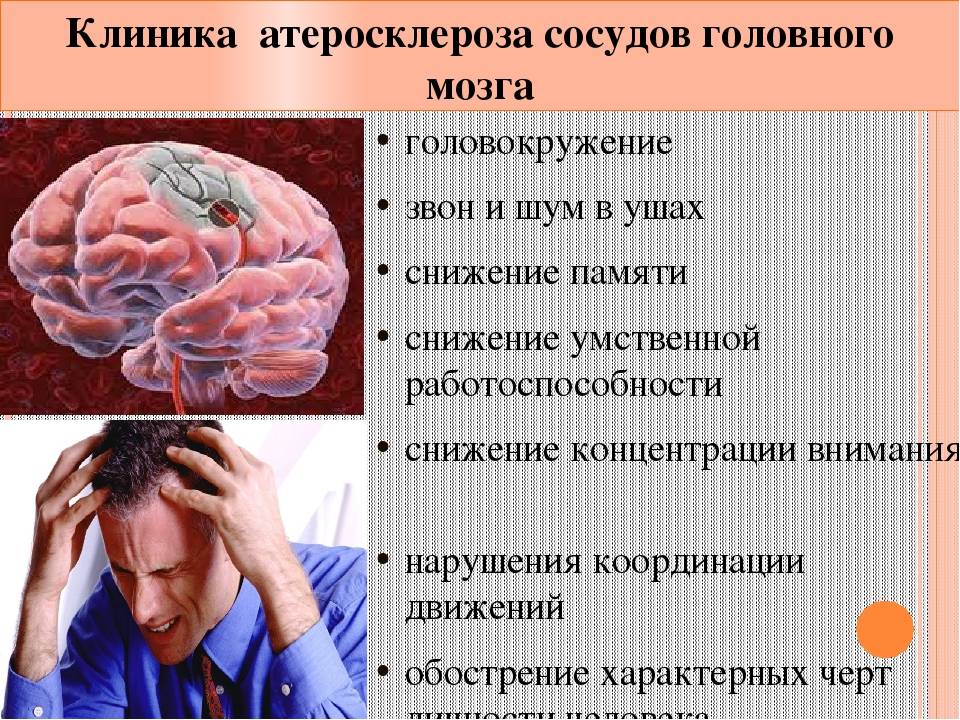

Проведите тест на координацию движений - невыполнение заданных движений может указывать на нарушения в работе сосудов головного мозга.

Проявите внимание к головной боли - выявление частых и интенсивных головных болей может быть связано с нарушениями кровообращения в головном мозге.

Проверьте зрение - изменения в зрительном восприятии могут быть связаны с проблемами сосудов головного мозга.

Изучите свое физическое состояние - слабость и одышка могут быть признаками проблем с сосудами головного мозга.